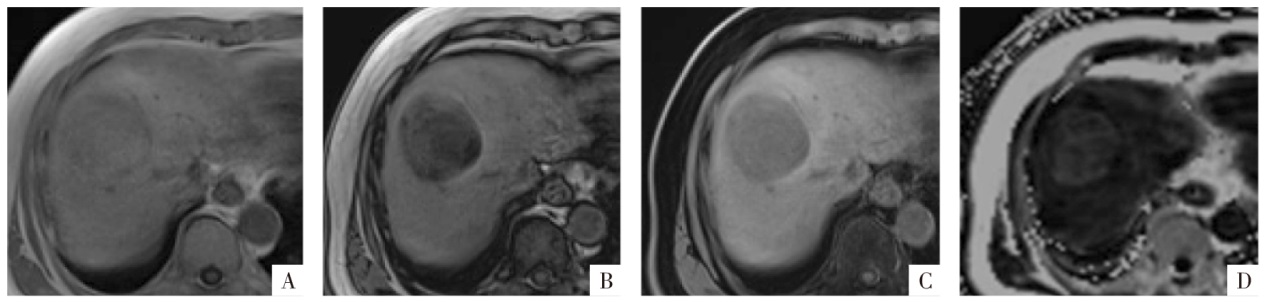

图2

脂肪变性MRI表现。病人男,67岁,肝细胞癌,病灶整体存在较严重的脂肪变性。A—D图分别为三维GRE序列T

1

WI同相位、反相位、水像(即脂肪抑制像)和PDFF图,病变在反相位(B)上整体信号较同相位(A)减低,水像(C)显示病灶信号减低程度较反相位弱。PDFF图(D)上相应病灶信号增高,PDFF约为16%。